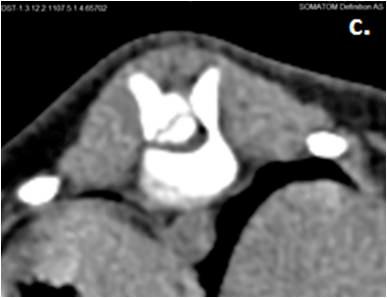

Examinăriile CT s-au realizat pe animale aflate sub anestezie generală injectabilă, cu xylazină 2% (Narcoxyl–MSD Animal Health) / acepromazină 2% (Aceprom-KEPRO B.V. OLANDA) – Propofol 1% (Fresenius Kabi), și poziţionate în decubit ventral sau dorsal. În baza datelor obținute prin scanarea pacienţilor prin intermediul aparatul Somatom definition AS (Siemens), s-a recurs la evaluarea imaginilor obținute, utilizând tehnica de reconstrucție multiplanară (MPR), dimensiunea secțiunilor fiind de 1 mm, iar - pentru o mai

ușoară vizualizare a leziunilor - și la reconstrucţia 3D a regiunii evaluate, utilizând tehnica de redare volumetrică VRT.

Afecțiunile decelate sunt: hemivertebre și vertebra intermediară la un Pudel (25% - rasă de talie mică, condrodistrofică), ostecondrită disecantă a sacrumului la un Ciobănesc german (25% - rasă de talie mare, necondrodistrofică), exostoze cartilaginoase multiple la un metis de talie medie (25%) și instabilitate atlanto-axială la un Chihuahua (25% - rasă de talie mică, necondrodistrofică).

Majoritatea câinilor prezintă un defect în partea dorsală a epifizei sacrale și un fragment osos detașat în canalul vertebral (4, 5) (fig. 1).

Figura 1. Osteocondrită disecantă sacrum şi protruzie discală tip 2

Figura 2. Instabilitate atlanto-axială secundară ageneziei procesului odontoid al axisului.